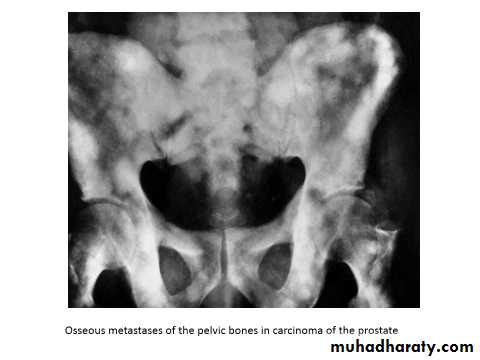

Blood: to the lower lumber vertebrae & pelvic bones due to reverse blood flow from vesicoprostatic plexus to the emissary veins of the bones (OSTEOBLASTIC changes)

Osteogenic : sclerotic in 65%, Osteolytic in 35%

Plain X ray: osteoblastic lesion.

Bone scan: hot areas (active).